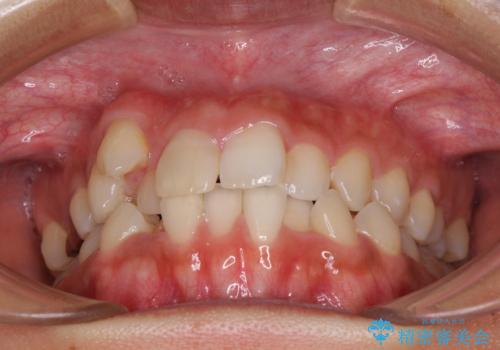

気になる八重歯 目立ちにくいハーフリンガルでの抜歯矯正

- 八重歯や前歯のデコボコを気にして来院された患者様です。

目立たない装置を希望されたので、上顎が裏側装置のハーフリンガルを選択し、上下左右の小臼歯(計4歯)を抜歯して矯正治療を行うこととしました。

補助装置を併用することで、八重歯を速やかに改善し、治療期間の短縮を図ることとしました。

裏側装置での矯正治療は、上顎前歯の正中のズレをまっすぐに改善することが難しいのですが、きれいに整えることができました。

補助装置を用いて抜歯したスペースを速やかに閉じたことで、短期間での治療となりました。